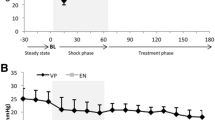

After instrumentation, animals were stabilized for 45 to 60 minutes (baseline phase T1). Then hemodynamic parameters and CNS pressures were recorded and CSF and blood samples collected. The next phase (T2) started with the introduction of a Veress needle through a small horizontal infra-umbilical incision into the peritoneal cavity. After connecting the Veress needle to the laparoscopic insufflator, a preset IAP of 20 mmHg was established mimicking intra-abdominal hypertension grade II. Helium was used for insufflation instead of CO2 in order to eliminate effects on blood gases [36]. IAP of 20 mmHg was maintained for 45 to 60 minutes and then pressures were recorded and samples collected as in phase T1. Phase T3 included a further rise of IAP by establishing a pneumoperitoneum of 45 mmHg for another 45 to 60 minutes, mimicking ACS, after which pressures were recorded and samples collected. Finally, the abdomen was desufflated by opening the Veress needle to the air (phase T4). After 45 to 60 minutes of animal stabilization, pressures were recorded and samples collected.

Cardiovascular system (Figures 1, 2, 3, 4 and 5)

Animals were considered normovolemic due to estimation of the preload status with traditional CVP measurement which was misleading. Calculation of the transmural intracardiac filling pressures revealed that animals were hypovolemic with an associated tachycardia (Figure 1). Heart rate initially decreased in phase T2, but was increased in the two subsequent phases, with a parallel increase in MAP and a decrease of APP (Figure 2). Cardiac output and cardiac index were decreased in phase T3 and restored to baseline levels after abdominal desufflation (Figure 3). Systemic and pulmonary vascular resistances increased significantly with IAH and decreased after abdominal desufflation (Figure 4). IVCP reflected accurately the changes in IAP (Figure 5).

Respiratory function and acid-base homeostasis (Figures 5, 6, 7)

IAH increased peak inspiratory pressure (PIP) in both phases T2 and T3, declining after abdominal desufflation (Figure 5). In contrary, pH was decreased during T2 and T3 and increased to baseline levels after removal of the pneumoperitoneum (Figure 6). This change was associated with an increase in pCO2 in the same phases, which returned to baseline levels after desufflation. A concomitant decrease in bicarbonate and base deficit were observed, without, in fact, compensating the acute respiratory acidosis (Figure 7). Finally, end-tidal carbon dioxide (EtCO2) varied between pre-established limits (35 to 45 mmHg) (Figure 7).